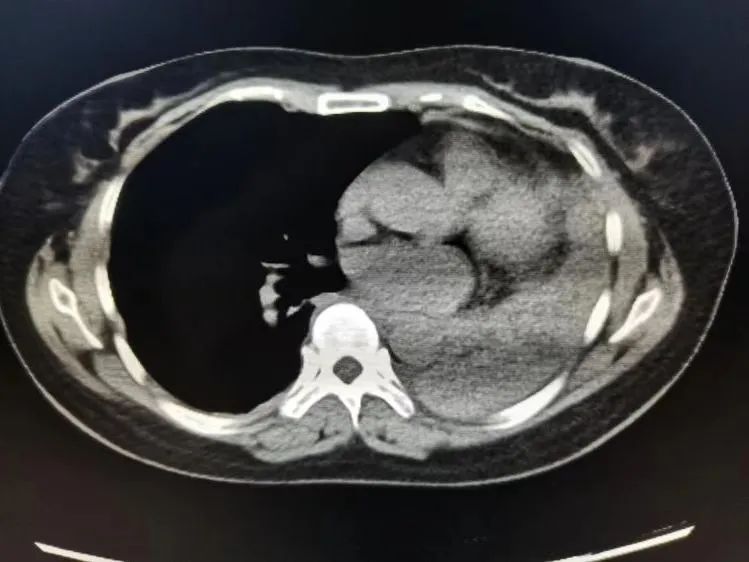

患者为女性,54岁,2021年2月4日晚上开始出现胸痛、呼吸困难,伴发热,3天后急诊入院。其左主支气管完全堵塞、左肺不张,病情进展快,有胸痛、发热、呼吸困难等症状,结合病情、体征及相关实验室检查,考虑气道异物可能性大,阻塞性肺炎。

同时,在支气管镜检查及新生物钳取过程中发现此物质软、表面光滑,钳取时易滑、易碎,且患者虽有经鼻高流量100%氧浓度的支持,仍缺氧明显,不能耐受,经反复尝试仅取出少量标本,送检后病理回报为异物。经讨论后决定行气管插管全麻下保证通气及氧饱和度的前提下给患者行气道异物取出术。

从麻醉、插管、镇痛镇静到异物取出、气道完全通畅历时3.5小时,在科室重症团队及呼吸介入团队的通力配合下成功取出异物,术后顺利脱机拔管,病人痊愈出院。这是科室首例独立完成的气管插管全麻条件下完成的呼吸介入治疗。